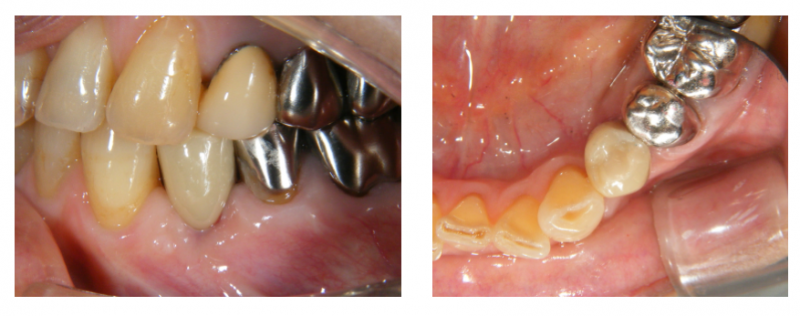

(写真左側)

歯型を採って、上部構造を作ります。

このケースもジルコニアです。

ネジで止めるシステムです。

(写真右側)

鏡にのせて写真を撮っています。

ネジ穴が咬み合わせの面の中心になるように

埋め込みしています。

口腔内にセットします。

骨造成した部分も、しっかり骨になっています。

ネジ穴を白い詰め物で塞いで完成です。